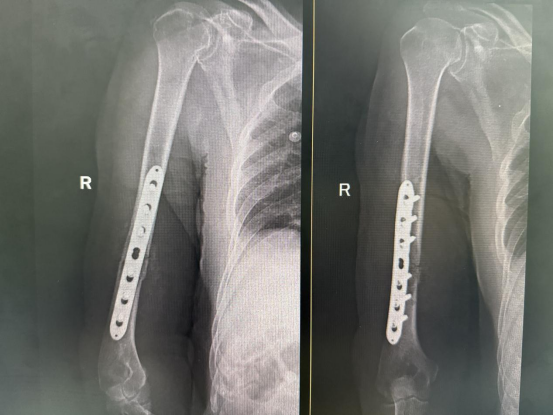

术前三维重建

术后DR复片